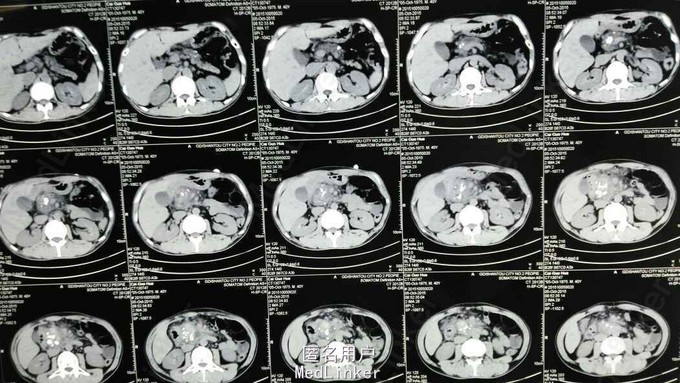

查体:T 36.4℃ P 104次/分 R 20次/分 Bp 109/75mmHg 急性痛苦面容,神志清,精神稍疲,对答切题,查体合作。全身皮肤黏膜无黄染、出血点,全身浅表淋巴结未扪及肿大。睑结膜无苍白,巩膜无黄染,双侧瞳孔等圆等大,直径约2.5mm,对光反射灵敏。颈软,无抵抗,颈静脉无怒张,双肺呼吸音稍粗,未闻及干、湿性啰音,心率104次/分,律齐。上腹肌紧张,腹平,未见肠型及蠕动波,左上腹、中上腹压痛,无反跳痛,肝脾触诊不满意,肝肾区叩痛(-),移动性浊音(-),肠鸣音活跃。辅助诊断:血常规示白细胞 5.9×10^9/L 中性粒细胞比率 61%,血红蛋白 151g/L,血小板341×10^9/L;(10-4)生化示葡萄糖5.14mmol/L,钾4.15mmol/L,钙2.21mmol/L,淀粉酶154U/L,脂肪酶357U/L;血气分析未见异常;腹部彩超示肝无明显占位,胆囊稍大,无结石,胰腺显示不清;腹部平片未见肠梗阻及消化道穿孔征象。入院后查上腹部CT:1.胰头部明显肿胀,呈混杂密度影,考虑炎症性改变并周围渗出,胰头部、胰管近端多发结石或钙化;肿瘤常规:甲胎蛋白 7.9ng/ml,癌胚抗原 1.31ng/ml,CA-199 3.84ng/ml;(10-5)生化:葡萄糖 4.48mmol/l,钙 2.19mmol/l,总胆红素 24.4umol/l,谷丙转氨酶 10U/L,淀粉酶142U/L,脂肪酶168U/L; 上腹部MRI+MRCP示考虑慢性胰腺炎急性发作,胰头部假性囊肿形成,胰头区多发钙化灶,未除外胰头Ca可能,请结合临床